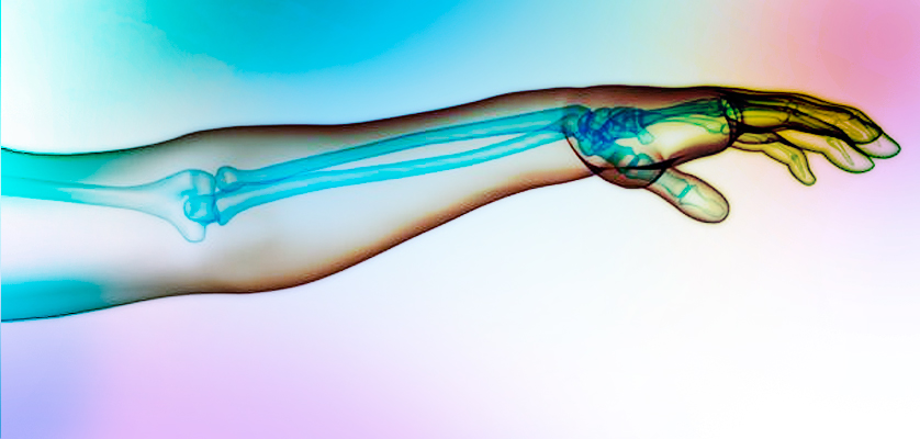

Estos descubrimientos podrían servir de base para futuros trabajos que exploren la regeneración en humanos, esto enfocado a los pacientes que han perdido sus extremidades por diabetes o traumatismos y que la posibilidad de recuperar la función mediante la regeneración natural esta fuera de su alcance.

Las ranas que recibieron el tratamiento mostraron aumentos a largo plazo en la longitud del hueso, el patrón de los tejidos blandos y la reparación neuromuscular; estas pudieron usar las nuevas extremidades para nadar, de forma muy parecida a como lo haría una rana normal.